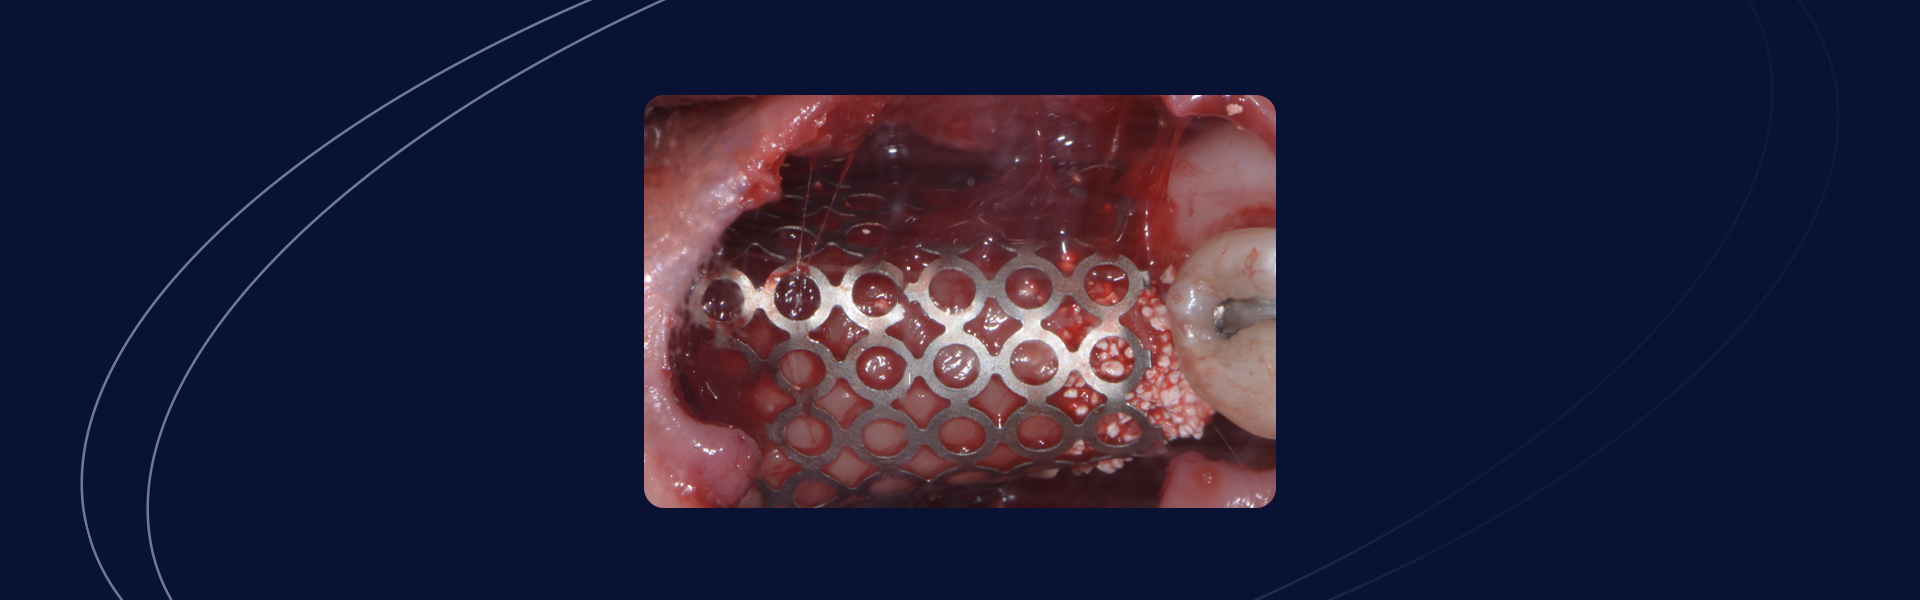

Reconstrução em região posterior de mandíbula e futura instalação de implante guiado

Prof. Dr Augusto Bessa Gênero e idade do paciente: Paciente E.M.Z., 47 anos, sexo feminino. Queixa principal: Insatisfação com ausência de dente em região posterior de mandíbula. Avaliação inicial: Após anamnese detalhada, exame clínico e radiográfico, foi verificada perda e altura em região posterior de mandíbula. Passo a passo Paciente compareceu com a necessidade de […]